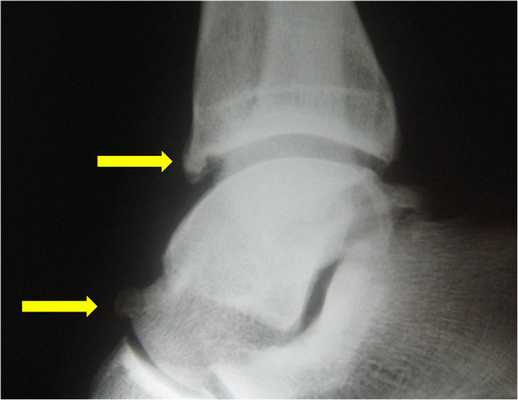

Ущемление капсулы сустава вместе с синовиальной оболочкой в области голеностопа, приводит к развитию импинджмента. В местах, где происходит сдавливание, начинают разрастаться остеофиты (иначе их называют костными шипами), развивается активный воспалительный процесс.

Наличие остеофитов приводит к еще большему уменьшению естественного пространства между таранной и большеберцовой костями. Как следствие, капсула сустава и синовиальная оболочка страдают еще сильнее, выраженность воспалительного процесса возрастает, усиливается болевой синдром.

Передний импинджмент - это в основном следствие травматического повреждения связочного аппарата голеностопа. Любая нестабильность сочленения, даже если она выражена совсем слабо, помогает его травматизации в положении крайнего разгибания.

По статистике, от переднего импинджмента в основном страдают атлеты. У них недуг спровоцирован частой высокой нагрузкой на переднюю часть сустава, что вызывает постоянные его повреждения. В первую очередь при данном недуге уменьшается амплитуда разгибания сочленения.

Задний импинджмент часто связно с анатомическими особенностями строения голеностопа и травмами. Задний тип импинджмента характерен в основном для балетных танцоров. Ведь во время этого танца человек вынужден много ходить на кончиках пальцев, что приводит к сильному сгибанию голеностопного сустава в задней части и, как следствие, к травматизации.

Пациенту обязательно назначают рентгенограмму. На рентгенологическом снимке доктор легко увидит остеофиты - костные разрастания, появившиеся из-за воспалительного процесса. Дополнительно выполняется снимок в стрессовом положении. На нем доктор определит, есть ли соударение костей.